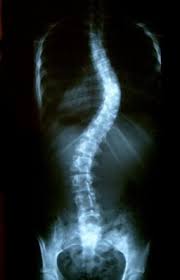

| Rx posterior de uma escoliose |

Hipócrates foi o primeiro a denominar a escoliose (sinuosa) como o desvio da coluna vertebral sobre o plano frontal. Existem porém outros componentes - inclinação lateral, lordose ou cifose, rotação e a torção que, somando-se ao desvio sobre o plano frontal, fazem com que a curva escoliótica assuma uma característica extremamente complexa, chamada por Perdriolle* de escoliose tridimensional.

As escolioses podem ocorrer em todos os seguimentos da coluna vertebral. Os desvios são classificados em: